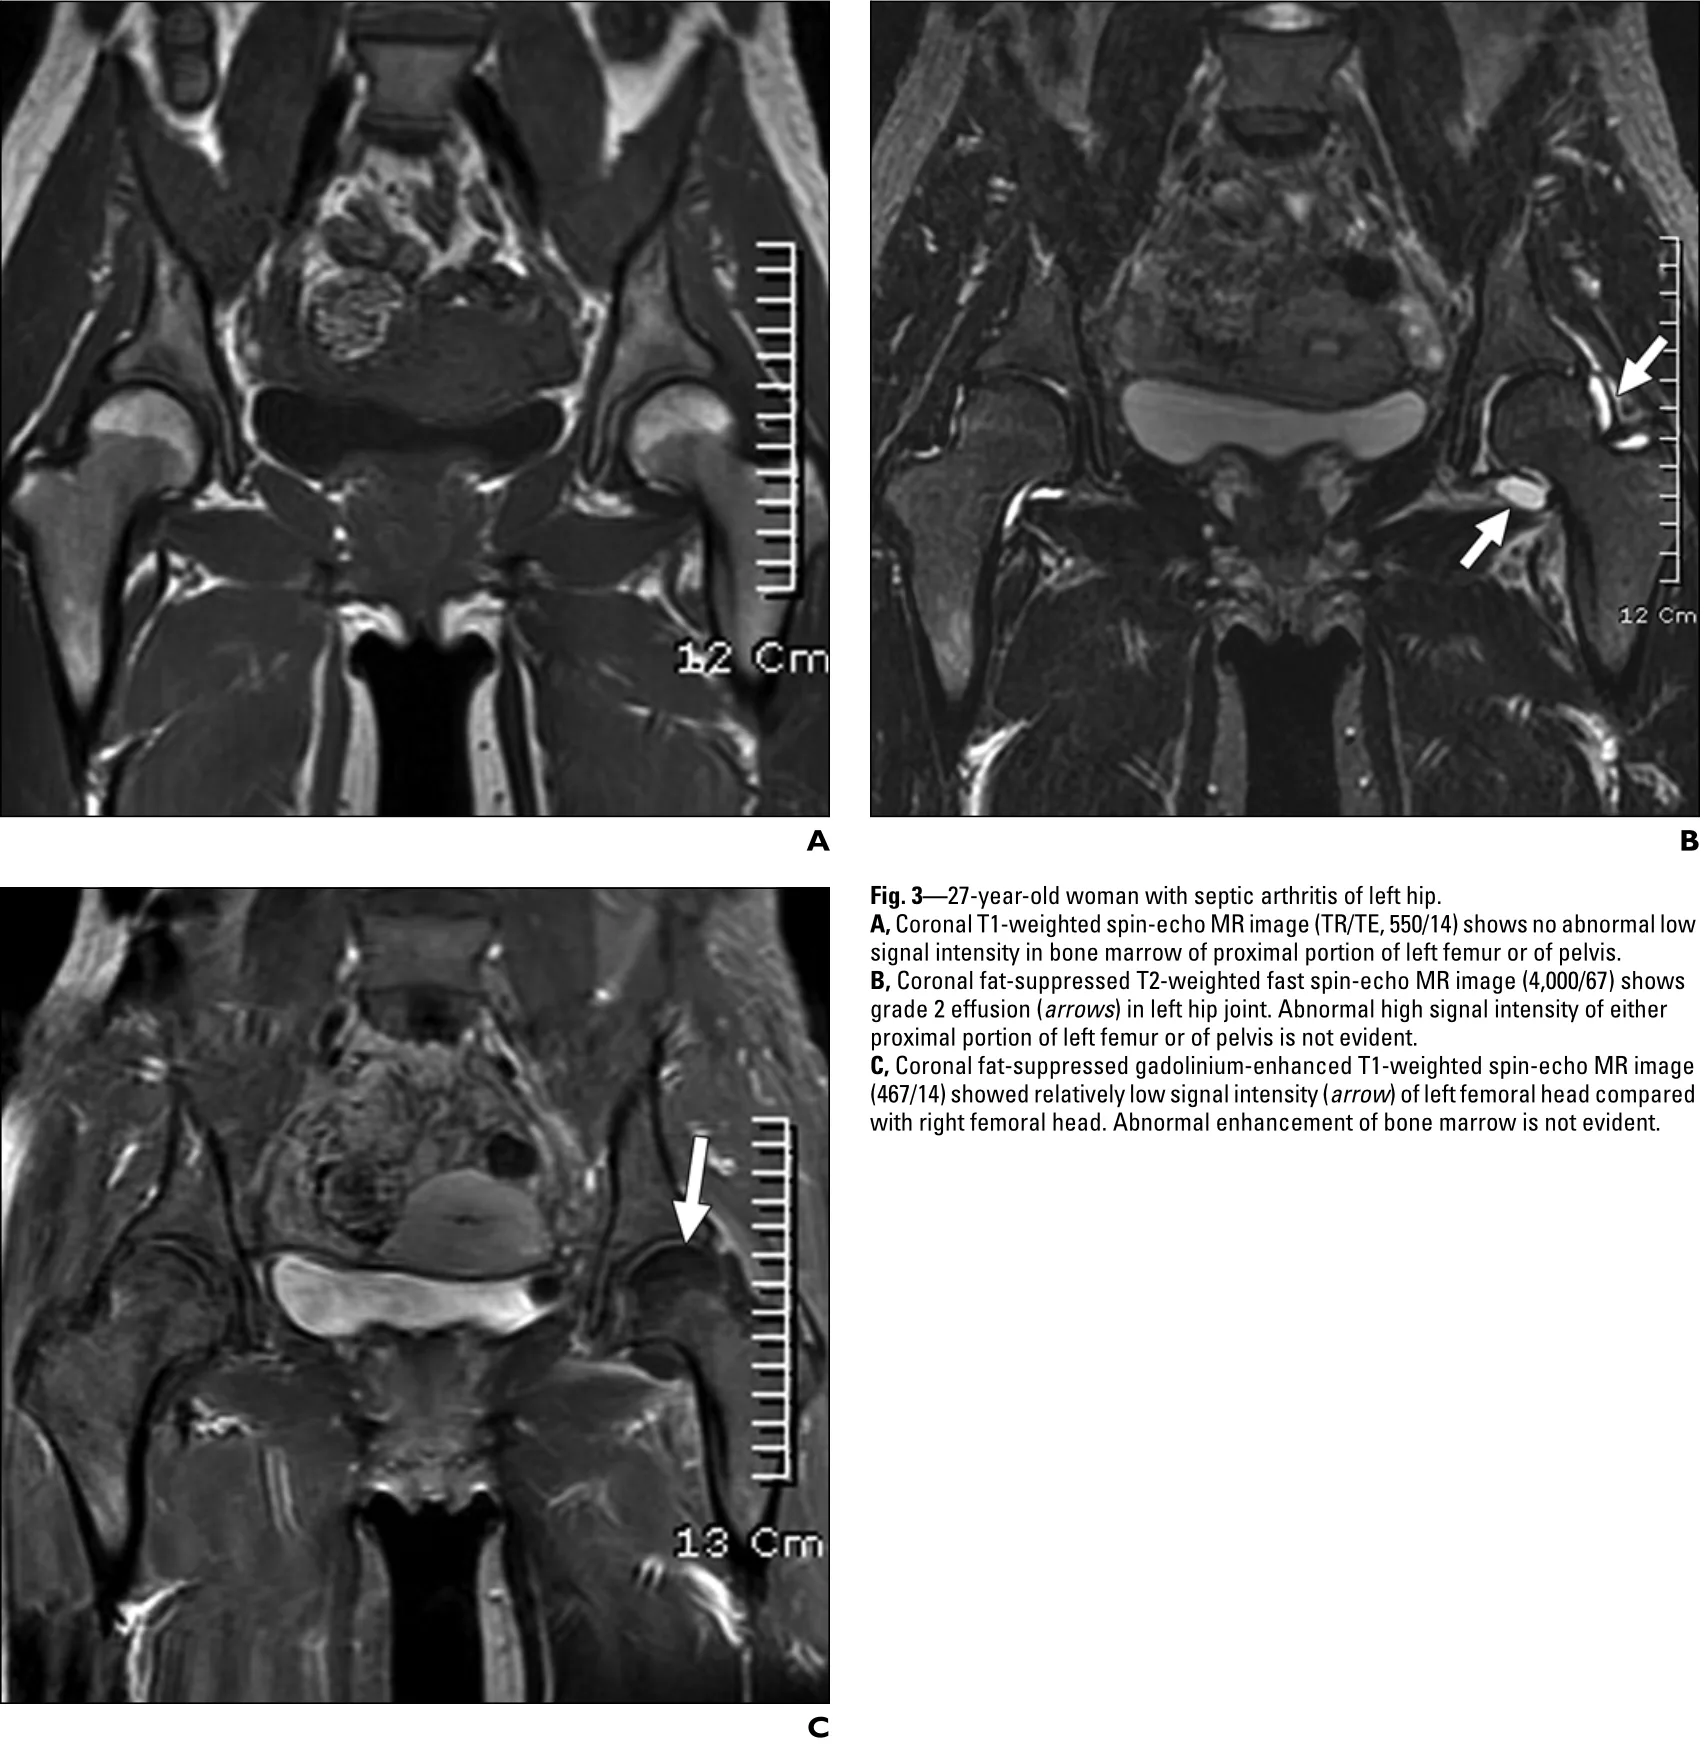

その結果, 白血球数が12,000/mm3, CRPが20.8 mg/dL(基準値0.3未満)と急性炎症所見を認めたので, 股関節のMRIを撮像することに.

脂肪抑制T2強調画像 (B)では, 炎症によって股関節の中に貯まった関節液が白く描出されています.

MRIの結果, 右股関節に液体の貯留を示す所見あり.

変形性股関節症で貯まった関節液なのか, 化膿性股関節炎や結晶誘発性股関節炎で貯まった膿性関節液なのかを鑑別する必要があります.

そこで, 股関節に針を刺して, 貯まった関節液を抜き取り, それを細菌学的検査と結晶同定検査に提出することにしました.